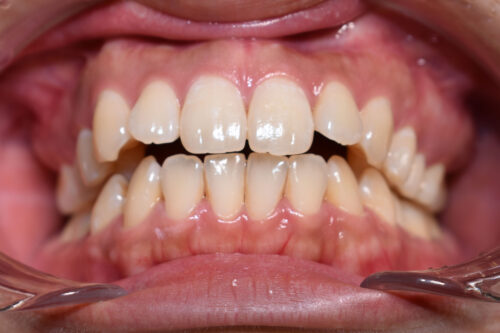

初診時年齢28歳女性

歯のがたつき(叢生)と

出っ歯

顔の長さを気になさり

巣鴨 ・ 池袋よりひとつ隣駅の東京都豊島区大塚駅すぐの大塚たまみ矯正歯科へ

来院されました。

かみ合わせは

奥歯が出っ歯方向へ

また 下方へ成長し ずれた状態で

開咬を呈しておりました。

ワイヤー矯正治療11か月後です。